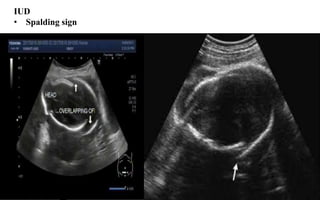

IUD

• Spalding sign